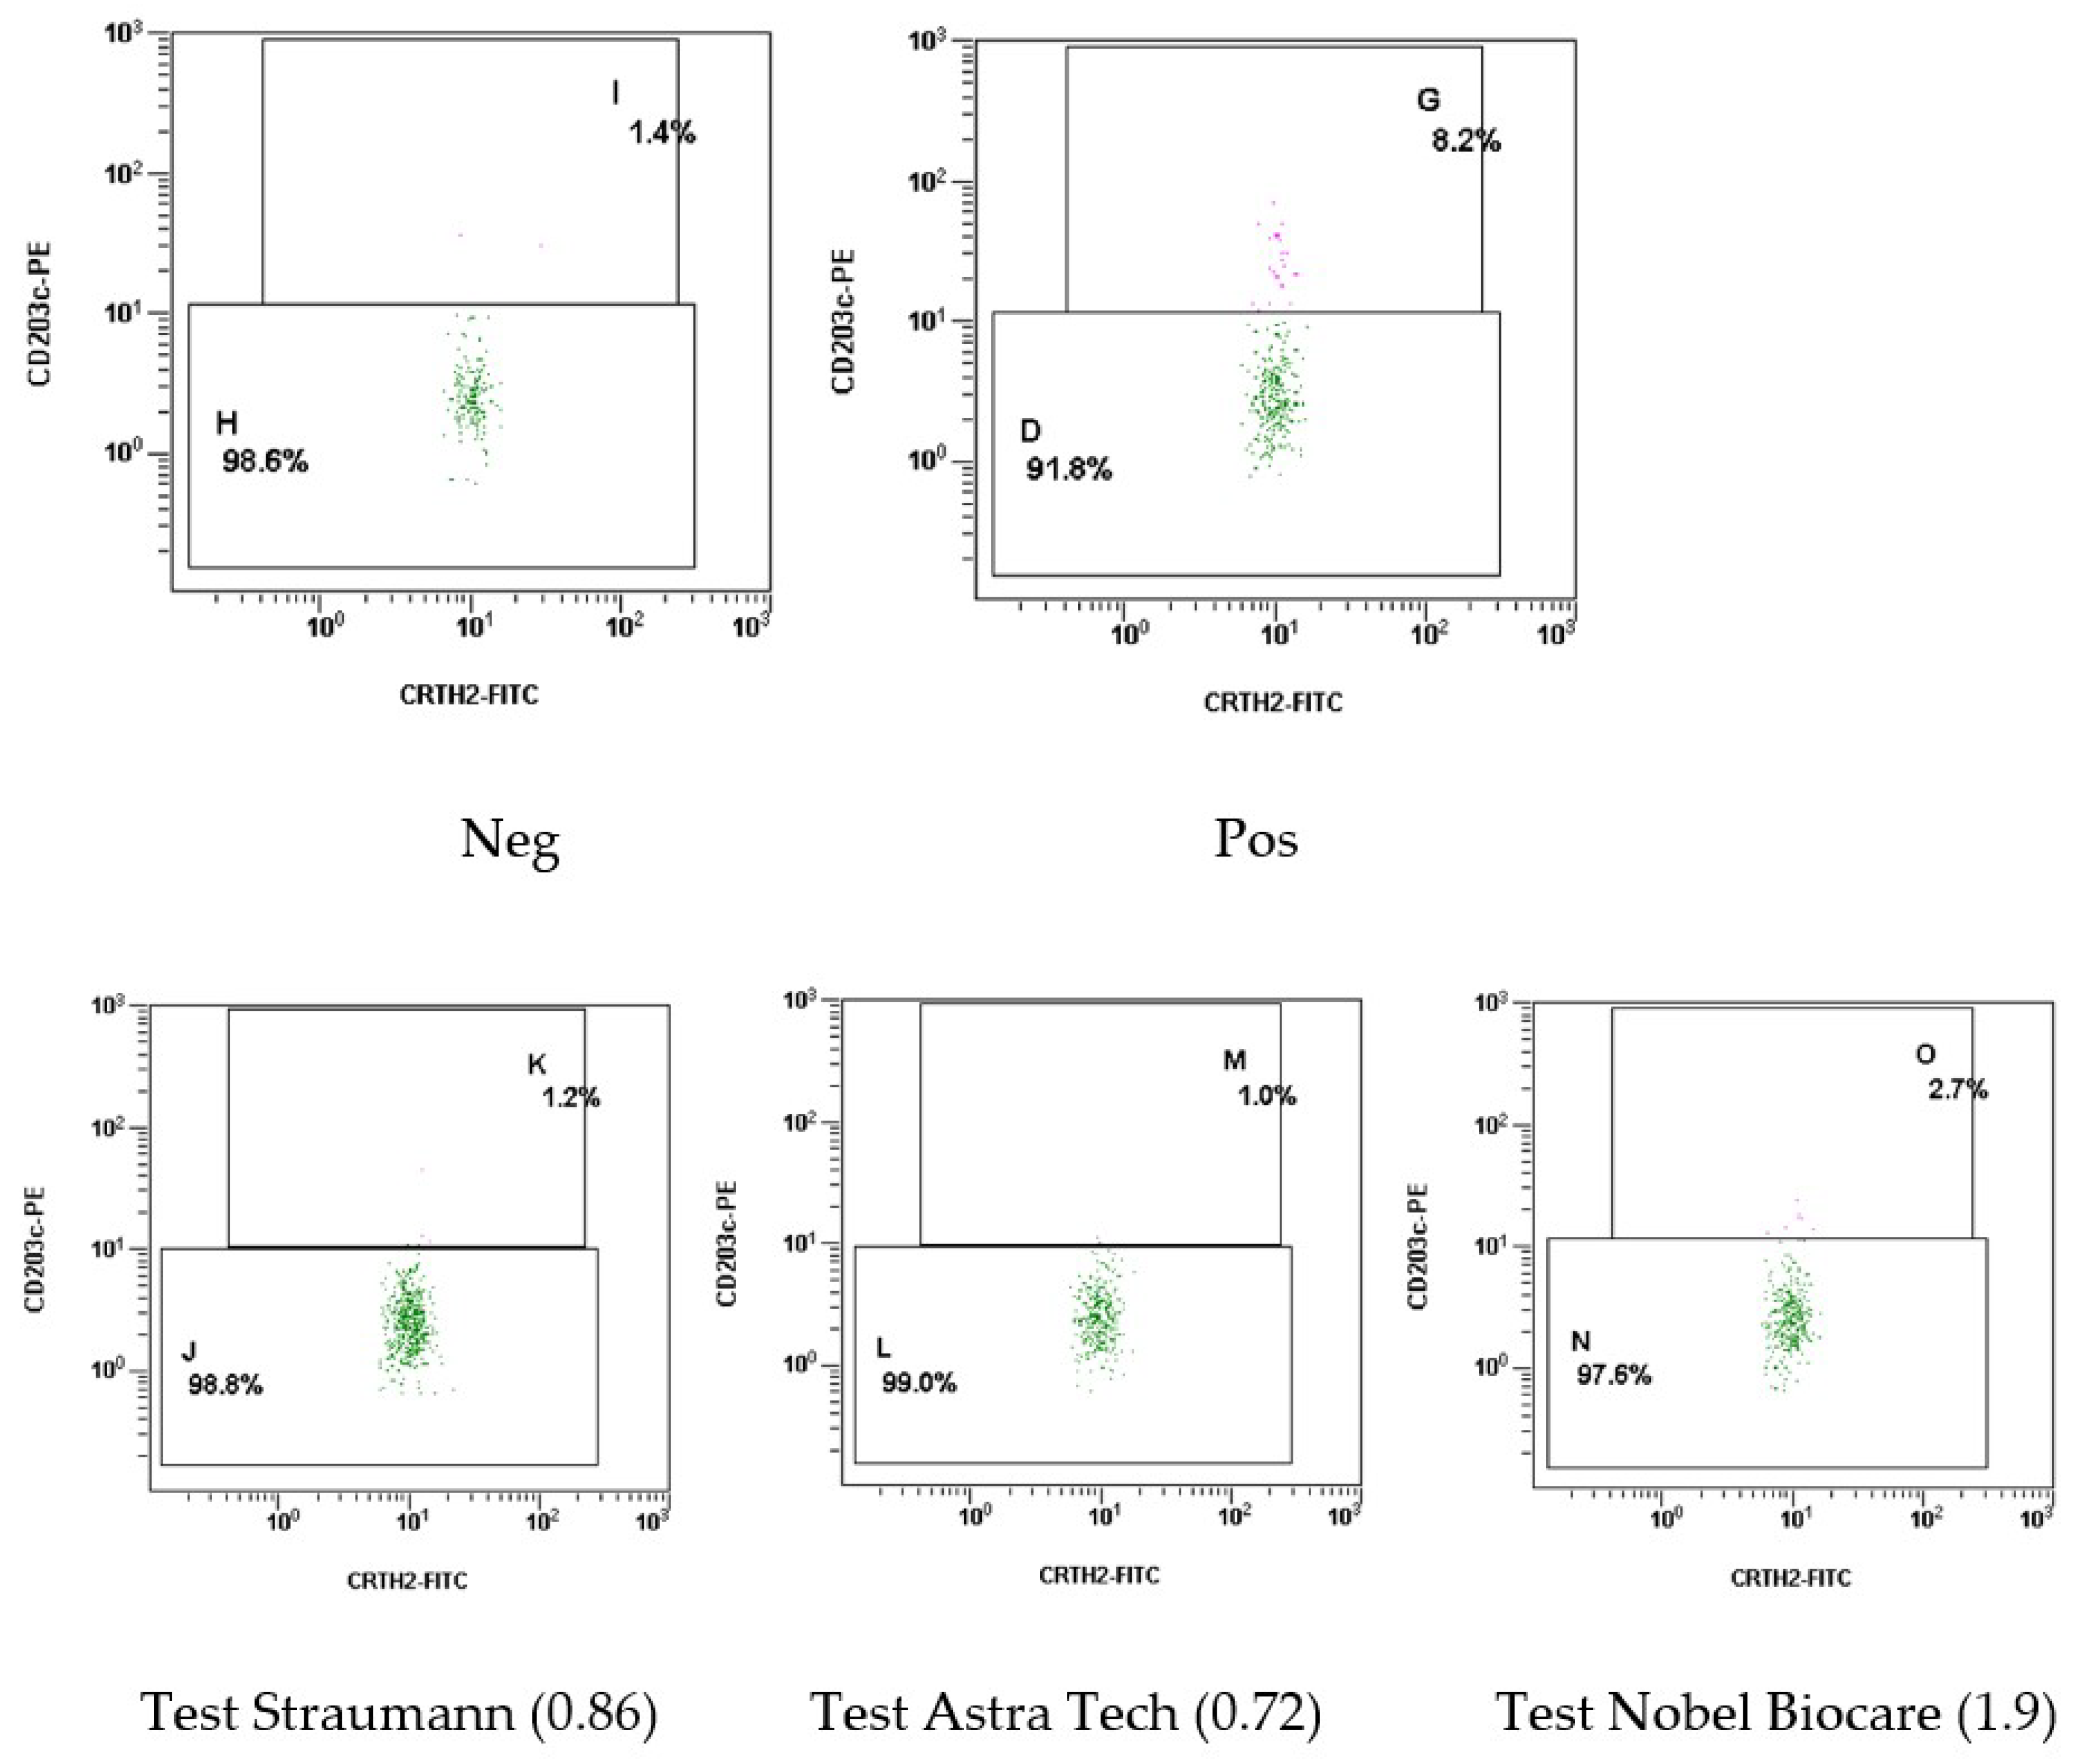

2.1.3. Results of the Basophil Test of Patient Sh. (Female, 52 Years Old)

4.6. Methodology for the Basophil Test